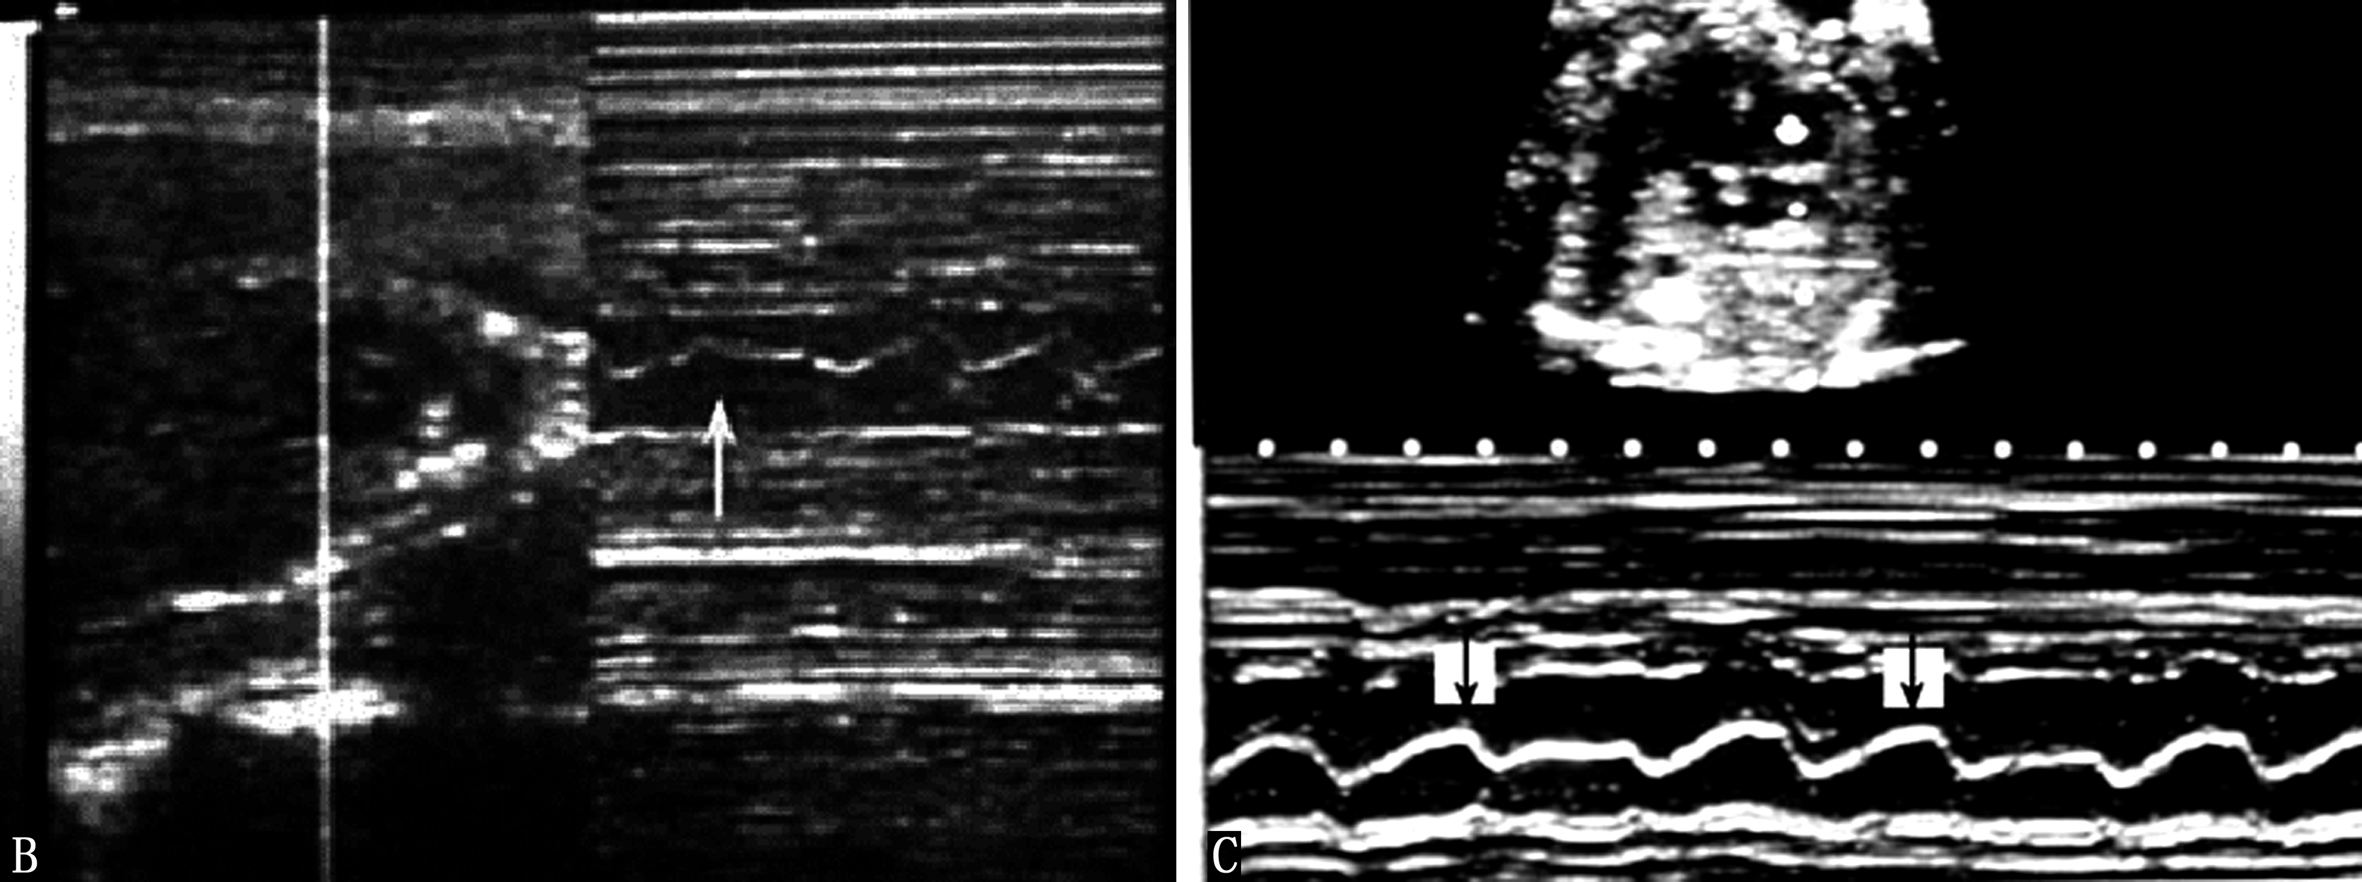

胎儿心律不齐并不少见,但病理性的心律不齐比较少见。和小儿一样,最常见的是窦性心律不齐和早搏。利用胎儿超声心动图和胎儿多普勒超声心动图可以很容易地记录胎儿心脏的异常搏动(图2A-C),并且由于心脏的异常搏动引起的异常血流频谱较心脏活动曲线更容易辨认,但能够提供给临床有价值的信息比较少。根据异常搏动对心室射血的影响程度以及代偿间期有时可以分辨异常搏动的来源,由于胎儿心率较快,分辨时多数有一定的困难。母亲因素,如情绪波动过大、疾病、饮酒、浓茶、过量的咖啡、子宫收缩等,胎儿的因素,如脐带受压、胎儿宫内窘迫、胎儿心脏畸形等均有可能引起胎儿心律失常。发现胎儿心律不齐时应密切观察复查,以判断其临床意义。严重的、持续存在的心律不齐,尤其是严重的室性心律不齐、阵发性心动过速等,可能由胎儿心脏的异常所致。缓慢而不规律的胎心活动常是胎儿凶兆之一。Copel等研究了来自4838个胎儿的5566份胎儿心脏超声检查记录。在595例心律不齐的胎儿中,330例(55.4%)没有发现异常,255例(42.9%)早搏,余10例的心律不齐对胎儿的血流动力学产生了一定的影响,其中9例预后良好,仅有2例合并有心脏发育异常。

图2-C胎儿心脏二联律引起的血流频谱的改变